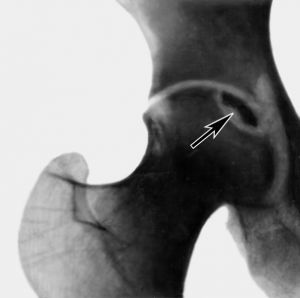

Следующий этап диагностирования — рентгенисследование поврежденной области. На начальных этапах, когда рентген не позволяет выявить некротические явления в кости, поэтому прибегают к сцинтиграфии костных структур либо магнитно-резонансной томографии. Последняя достаточно результативна при диагностировании на начальных этапах.

Врач способен заподозрить этот патологический процесс при наличии у пациента факторов риска и предъявлении им на локализованное болевое ощущение в кости. Болевой синдром при патологическом состоянии в области коленного или тазобедренного сочленений ухудшает ходьбу либо подъем тяжестей.

Хирургическая терапия показана для снижения болевого ощущения и предотвращения сплющивания головки тазобедренного сочленения в результате нагрузки.

При ухудшении состояния больного необходима декомпрессивная оперативная процедура. Она предусматривает просверливание в головке поврежденной кости миниатюрных отверстий, приводящих к уменьшению внутрикостного давления и предотвращению сплющивания.